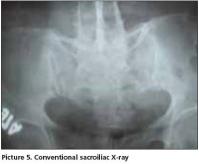

Her postero-anterior chest x-ray was evaluated as normal. In thoracic (Picture 1) and lumbosacral (Picture 2) graphs, marked squaring in her vertebras, shiny corners, symmetric syndesmophytes, bamboo spine, trolley track sign, osteoporosis and left faced scoliosis were observed. In pelvic x-ray her sacroiliac joints were normal. There were enthesopathic changes in the localization of the insertion of achilles tendon in calcaneus posterior bilaterally (picture 3). In magnetic resonance imaging (MRI) and conventional radiography, bilateral sacroiliac joints were regular and joints cartilage were normal (Picture 4,5). There were not any pathological signal changes in the bone surfaces that form the joints and the soft structures that were examined. Depending on the current clinical status and the radiography and imaging tests, the patient was defined as spondyloarthropathy (SpA).

Diagnosing axial SpA [Ankylosing Spondylitis (AS) and undifferentiated SpA(uSpA) with predominant axial involvement but without radiographic sacroiliitis] in the absence of radiographic sacroiliitis poses a major challenge to many physicians. In the absence of diagnostic criteria, classification criteria are often used to aid the diagnostic process in daily practice. The most often cited classification criteria for SpA are the Europian Spondylarthropathies Study Group (ESSG) criteria that were proposed in 1991. According to these criteria, in the absence of sacroiliitis; patients with inflammatory spinal pain or synovitis (asymmetric, predominantly in the lower limbs) in addition to any one of the following (positive family history, psoriasis, inflamatory bowel disease, alternate bottock pain, enthesopathy) are classified as seronegative SpA with 77% sensitivity and 89% specificity. In the presence of sacroiliitis, sensitivity is 86% and specificity is 87%[1]. However in a recent study from Spain, it was observed that the performance of the ESSG criteria as diagnostic criteria in daily practice was moderate: only 46.6% of patients with possible SpA who met the ESSG criteria at entry into the study were judged by their rheumatologist to have SpA after 5 years of follow up[2]. The typical radiographic changes of AS are seen primarily in the axial skeleton, especially in the sacroiliac, discovertebral, apophyseal, costovertebral, and costotransvers joints[3]. Syndesmophyits seen in AS and entheropathic arthiritis are usually symmetrical and bilateral, while that are seen in reactive arthiritis and psoriatic arthritis are nonmarginal, rough and asymmetrically located[4]. The radiological appearance of arthritic changes in sacroiliac joints has been regarded as a hallmark of AS according to Modified New York Criteria[5]. In AS patients in addition to sacroiliitis, arthritic changes in the spine visualized by x-ray develop in 57- 88% of the patients[6,7]. In literature, there were AS patients with typical clinical features but no radiological sacroiliitis[8]. Khan et al reported that radiographic sacroiliitis is frequent in AS but is not an early or obligate manifestation of the disease. In particular, relatives of AS with IBP may not show radiographic sacroiliitis even after long follow-up[9]. Rudwaleit reported that in a small proportion of AS patients may never develop radiolographic sacroiliitis despite having IBP for many years. SpA patients with predominantly axial symptoms should be considered as having a same disease entity as AS patients, independent from the presence of radiographic sacroiliitis[10]. In one study 60% of SpA patients had developed definite AS after 10 years of follow-up. It took an average of 9 years (+/-6 years) for radiological sacroiliitis to appear in these patients. A further 20% still had chronic uSpA and might have developed radiological sacroiliitis if their follow-up had been continued for a longer time[11]. Again in another family study, radiographic evidence of sacroiliitis was found in 40% of patients with a symptom duration of <10 years, 70% with symptoms for 10-19 years, and 86% with symptoms for ≥ 20 years[12]. The morphological changes used to assess spinal involvement in x-ray were syndesmophytes, shining corners, squaring, arthritis of the apophyseal joints, spondylodiscitis, bamboo spine and trolley track sign[13]. Descriptions of spinal x-ray changes typical of AS without concomitant radiological sacroiliitis are thus relatively uncommon. Besides, Moll reported that these spinal x-ray changes develop later in the course of AS and usually after radiological sacroiliitis is evident.[14]. MRI is considered to be very helpful in detecting signs of sacroiliitis that are not yet visible in x-ray[15]. Although our HLA B27 positive patient has been suffering from IBP for 10 years, no sacroiliitis was detected in her pelvic x-ray and MRI. However in her throracic and lomber x-ray, all radiological abnormalities such as squaring, shiny corner, syndesmophytes, bamboo spine, trolley track sign were clearly present. In her foot x-ray, bilateral calcaneal enthesopathy was detected.